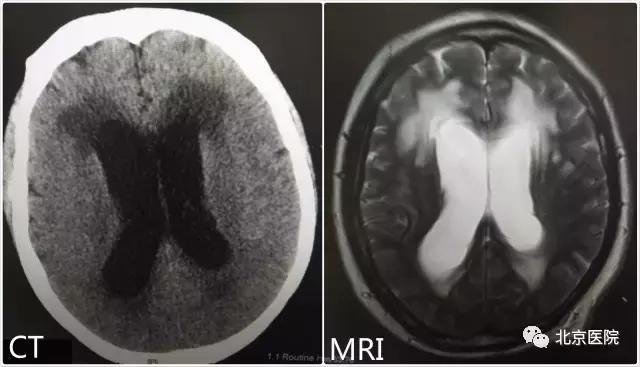

特发性正压性脑积水起病隐匿,其发病机制不清,与颅内出血、炎症以及脑顺应性下降等因素有关,由于脑脊液在脑内过多聚集,CT和磁共振检查可以发现脑室扩大,重要的是,它的手术治疗效果颇佳。